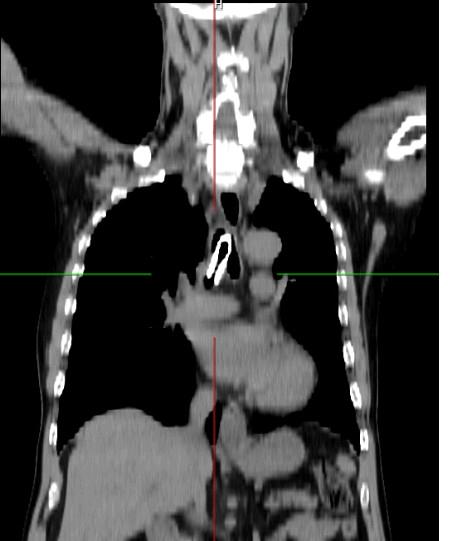

Hình ảnh canuyn gãy được gắp qua can thiệp ống cứng

Đến 13h30 ngày 18/10/2022 bệnh nhân được can thiệp nội soi phế quản ống cứng lấy dị vật. Sau 2 giờ làm việc căng thẳng, với sự tập trung cao độ của đội ngũ y bác sĩ, dị vật (đoạn canuyn gãy) đã được lấy ra, bệnh nhân ổn định và được chuyển lại Trung tâm Hô Hấp tiếp tục theo dõi. Ngày 20/10/2022, sau 2 ngày can thiệp, bệnh nhân tỉnh, không khó thở, không sốt, còn ho ít đờm, sức khỏe ổn định và đã được xuất viện vào ngày 25/10 trong niềm vui của gia đình và các thầy thuốc.